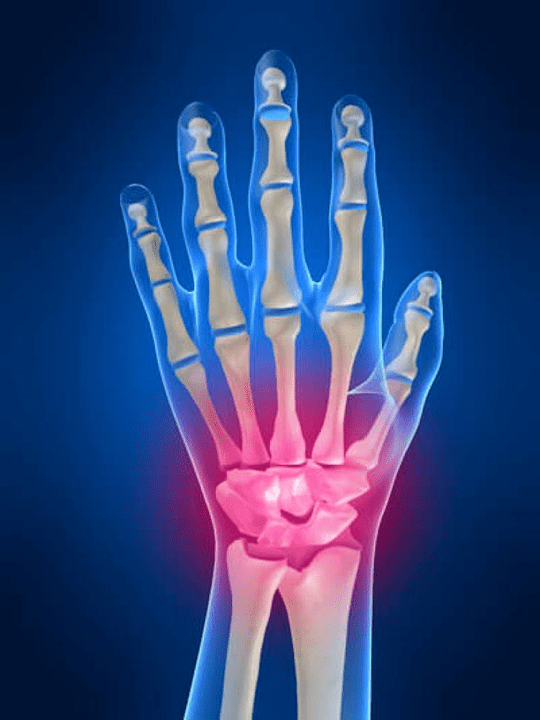

Gewrichtspijn Vingers zijn een onmisbaar teken van elke gewrichtspathologie waarin de structurele componenten van deze gewrichten zijn beschadigd. Allereerst kan pijn op het gebied van deze gewrichten worden geassocieerd met verschillende auto -immuunziekten (Systemische rode glans, reumatoïde artritis, psoriatica -artritis, enz.) waarin immuunfactoren schade veroorzaken aan hun eigen gewrichtsweefsels.

De volgende belangrijkste reden die kan initiëren pijn In de gewrichten van de vingers kunnen er verwondingen zijn (kneuzingen, dislocaties, botbreuken, ligamenten). Pijn in deze gewrichten kan ook worden veroorzaakt door degeneratieve veranderingen die zich voordoen in hun articulaire weefsels. Dit kan vaak worden waargenomen met artrose.

Het polsgewricht

Het polsgewricht wordt gevormd door de botten van de proximale botten (bovenste) Een aantal polsen (Trihedral, semi -moon, scaphoid botten) en distale gebieden van straling en elleboogbeenderen. Het elleboogbot is niet direct verbonden met de botten van de pols, maar met behulp van distale (Lager) de articulaire schijf. Deze structuur scheidt de holte van het polsgewricht van de distale holte (Lager) Het tegelgewricht.